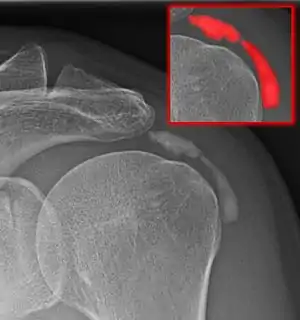

Calcific bursitis refers to calcium deposits within the bursae. This most occurs in the shoulder area. The most common bursa for calcific bursitis to occur is the subacromial bursa. A bursa is a small, fluid-filled sac that reduces friction, and facilitates movements between its adjacent tissues (i.e., between tendon and bone, two muscles or skin and bone). Inflammation of the bursae is called bursitis.

ULtrasound of calcific bursitis